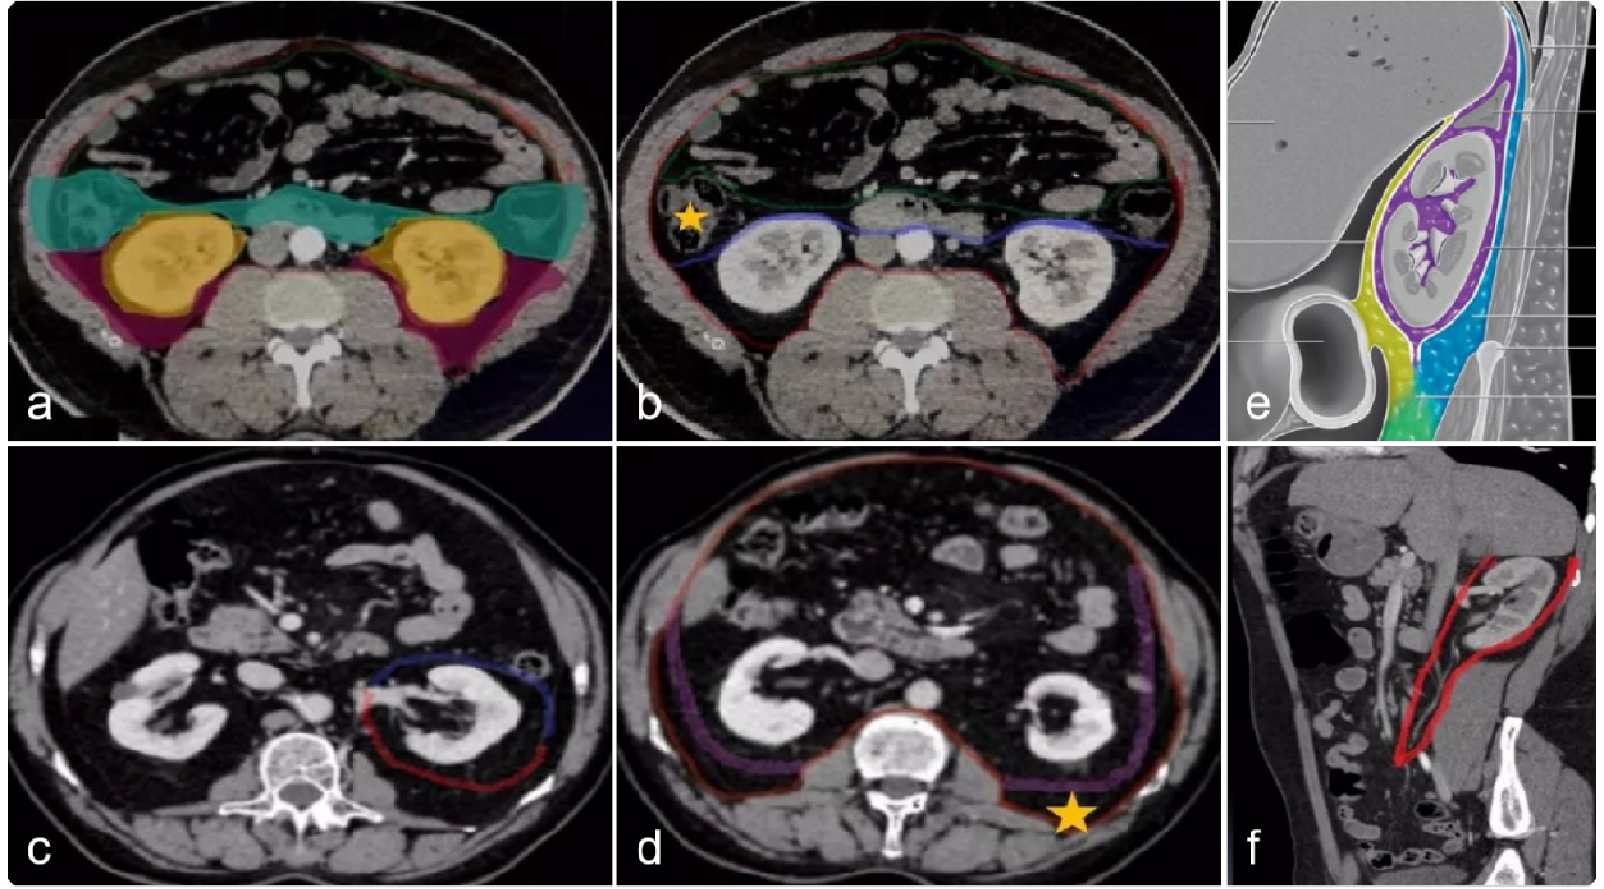

腹膜后神经源性肿瘤是比较常见的腹膜后肿瘤,在腹膜后肿瘤中居第二位,仅次于间叶组织来源肿瘤。多为圆形及卵圆形,界限非常清楚,瘤内血管较丰富,肿瘤多为软组织,有囊变的倾向,绝大多数肿瘤内均可见大小不等的囊变区,甚至全部肿瘤均为囊性,类似于单纯囊肿。儿童原发性腹膜后肿瘤绝大多数为神经源性肿瘤,如神经母细胞瘤。

腹膜后的神经源性肿瘤可源于腹膜后任何神经结构,主要位于腹膜后肾上腺区及沿脊柱两侧神经链分布。一般包括体神经来源的和交感神经起源的肿瘤。

体神经来源肿瘤主要来自腹膜后的脊椎神经,包括第12胸神经前支及腰骶神经干的所有分支。包括神经鞘瘤和神经纤维瘤等。在组织学起源上,神经鞘瘤(Schwannoma)和神经纤维瘤(Neurofibroma)分别起源于神经膜和神经纤维。

在交感神经细胞胚胎的发育过程中,一些细胞脱落进入肾上腺髓部与其结为一体,另一些细胞则演变为神经母细胞,继而变为交感神经节,根据节细胞和成神经细胞的构成比例分为节细胞瘤(Ganglioneuroma, GN),也称神经节细胞瘤、节细胞神经瘤和神经母细胞瘤(Neuroblastoma,NB)等。

一些细胞则演变为嗜铬细胞组织,主要沿腹主动脉及其分支生长成为副交感神经节链,其中最大一个神经节位于肠系膜下动脉根部。这些细胞虽有嗜铬特点,但不一定都属功能性,一旦这些细胞发生肿瘤,能分泌升压物质儿茶酚胺者为嗜铬细胞瘤(Pheochromocytoma,PCC),而无分泌功能者则多为副神经节瘤(Paraganglioma,PGL)。这些肿瘤均具有恶变的可能。

由于腹膜后间隙较宽松、广泛, 故腹膜后神经源性肿瘤常体积很大,但临床症状一般不典型,发现较晚,腹部肿块为首发症状。